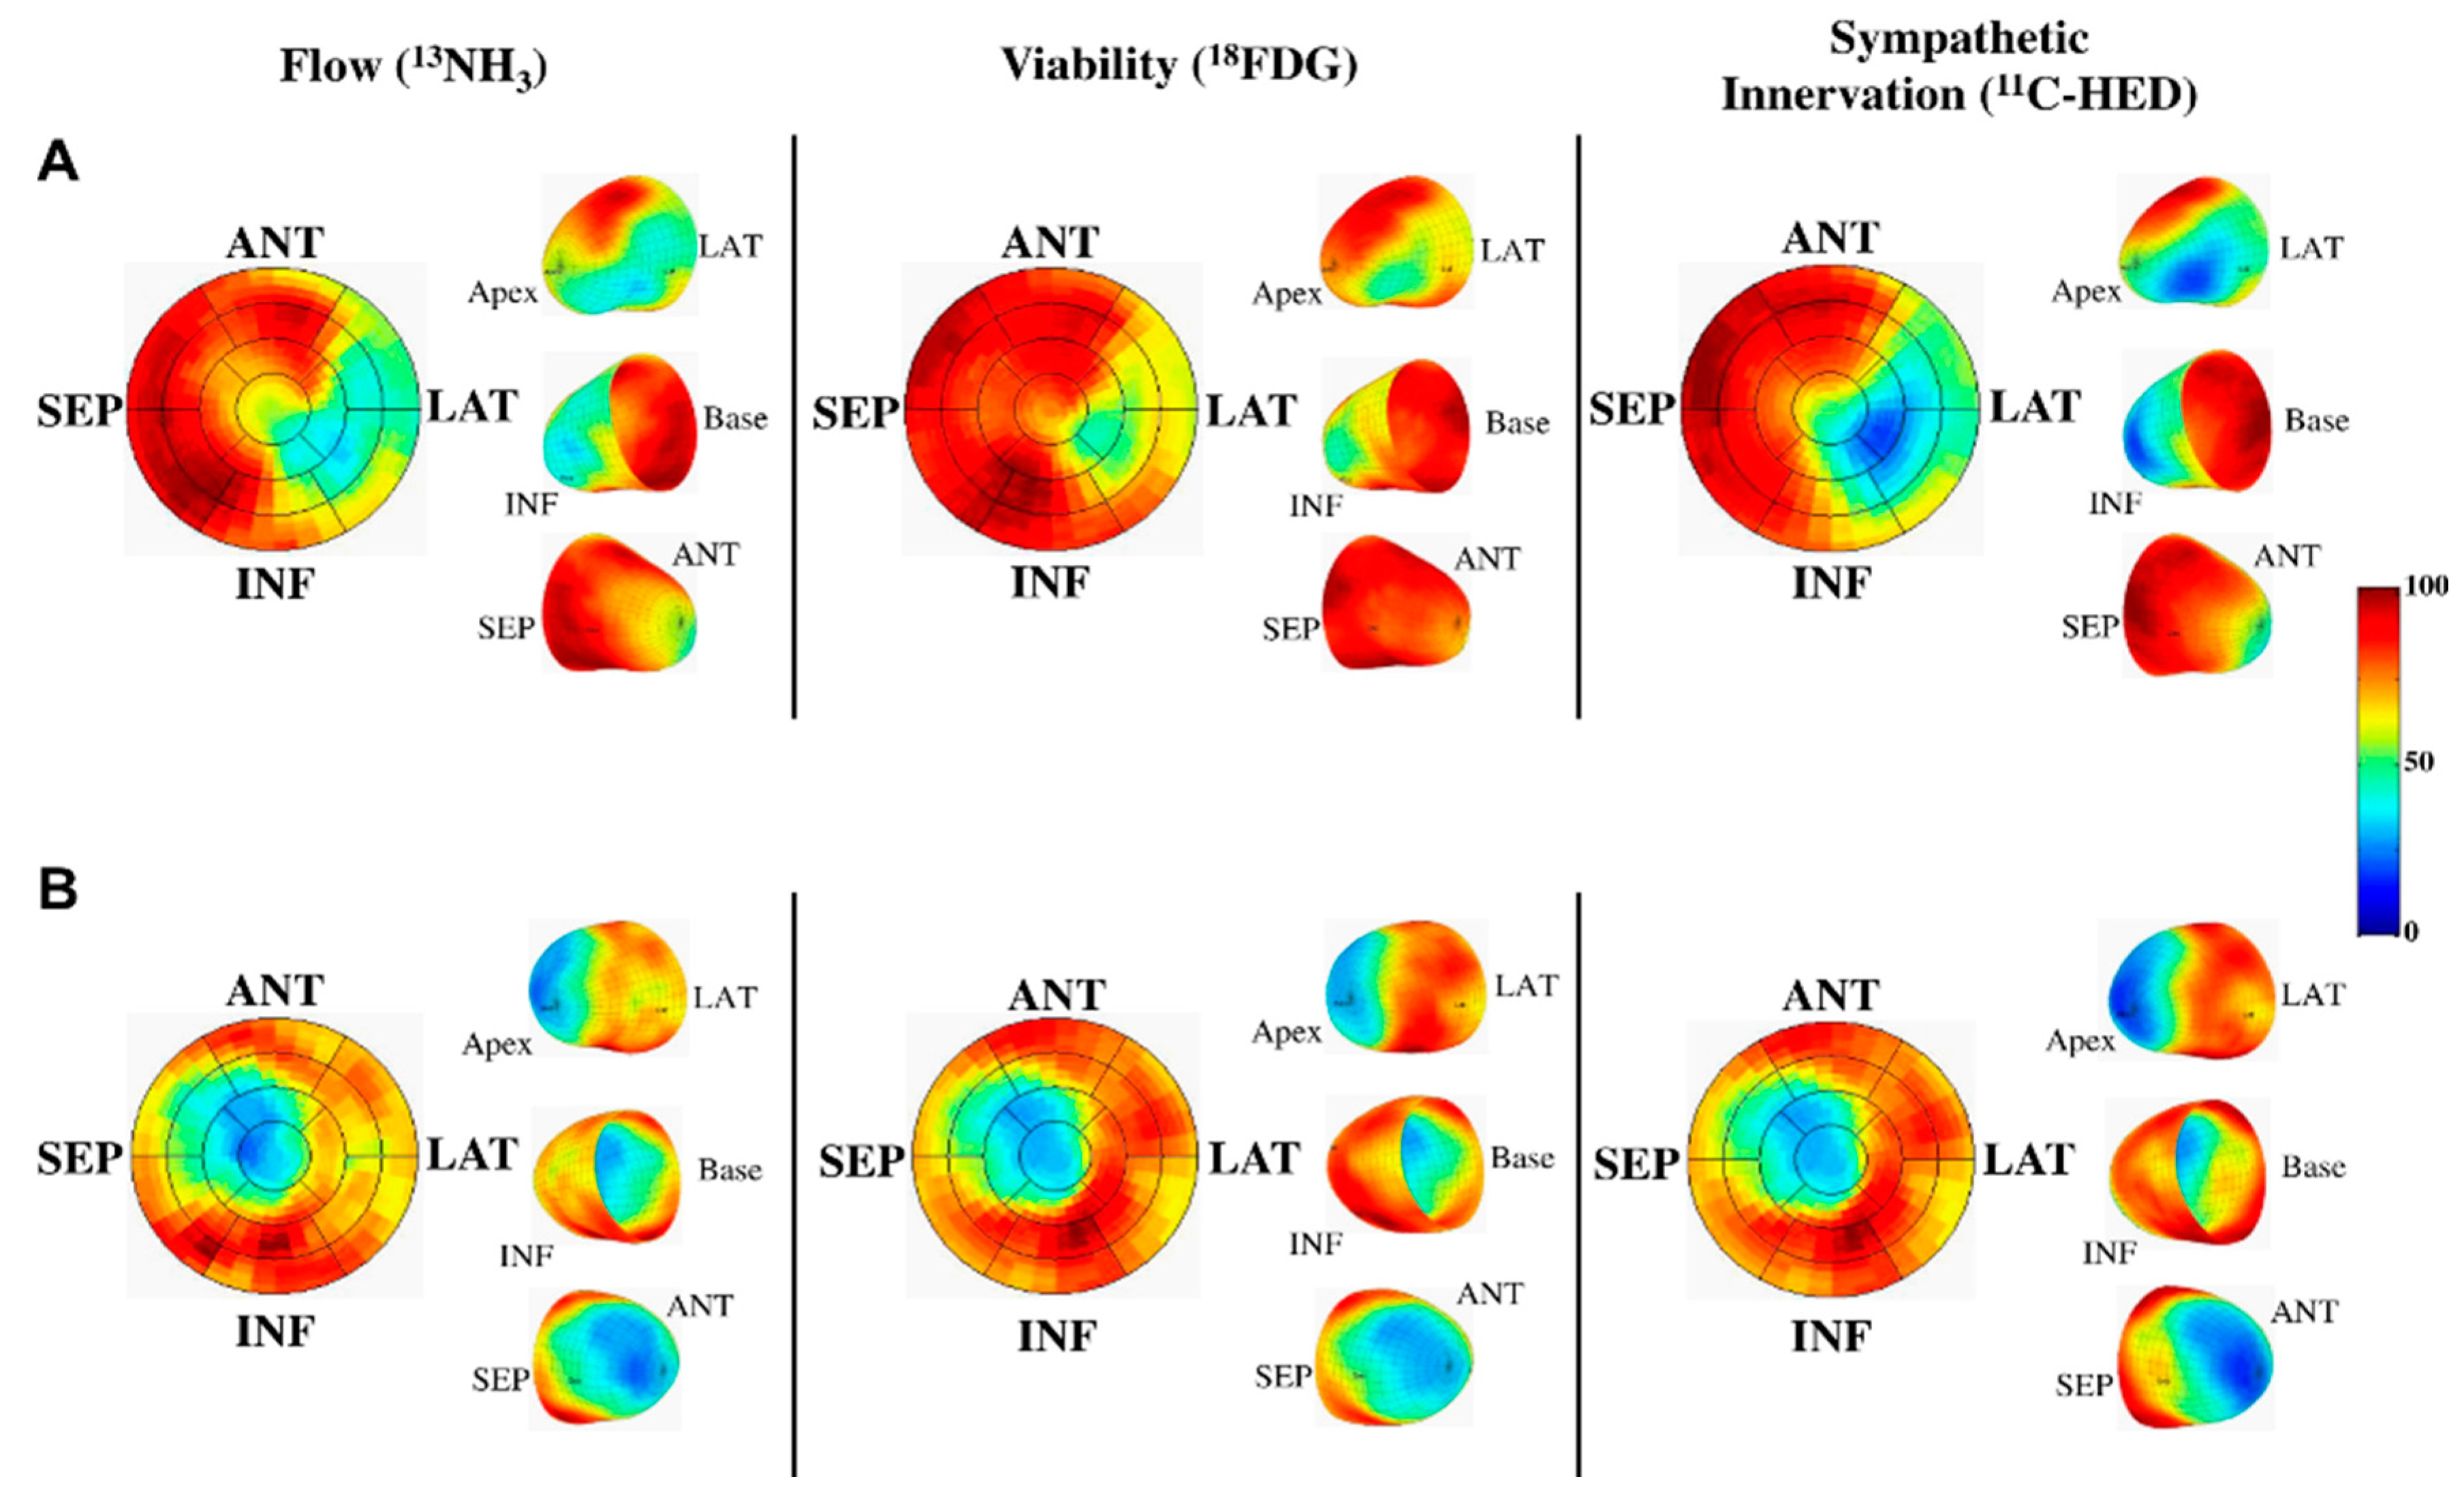

5.3. Heart Failure

5.4. Infiltrative and Inflammatory Processes